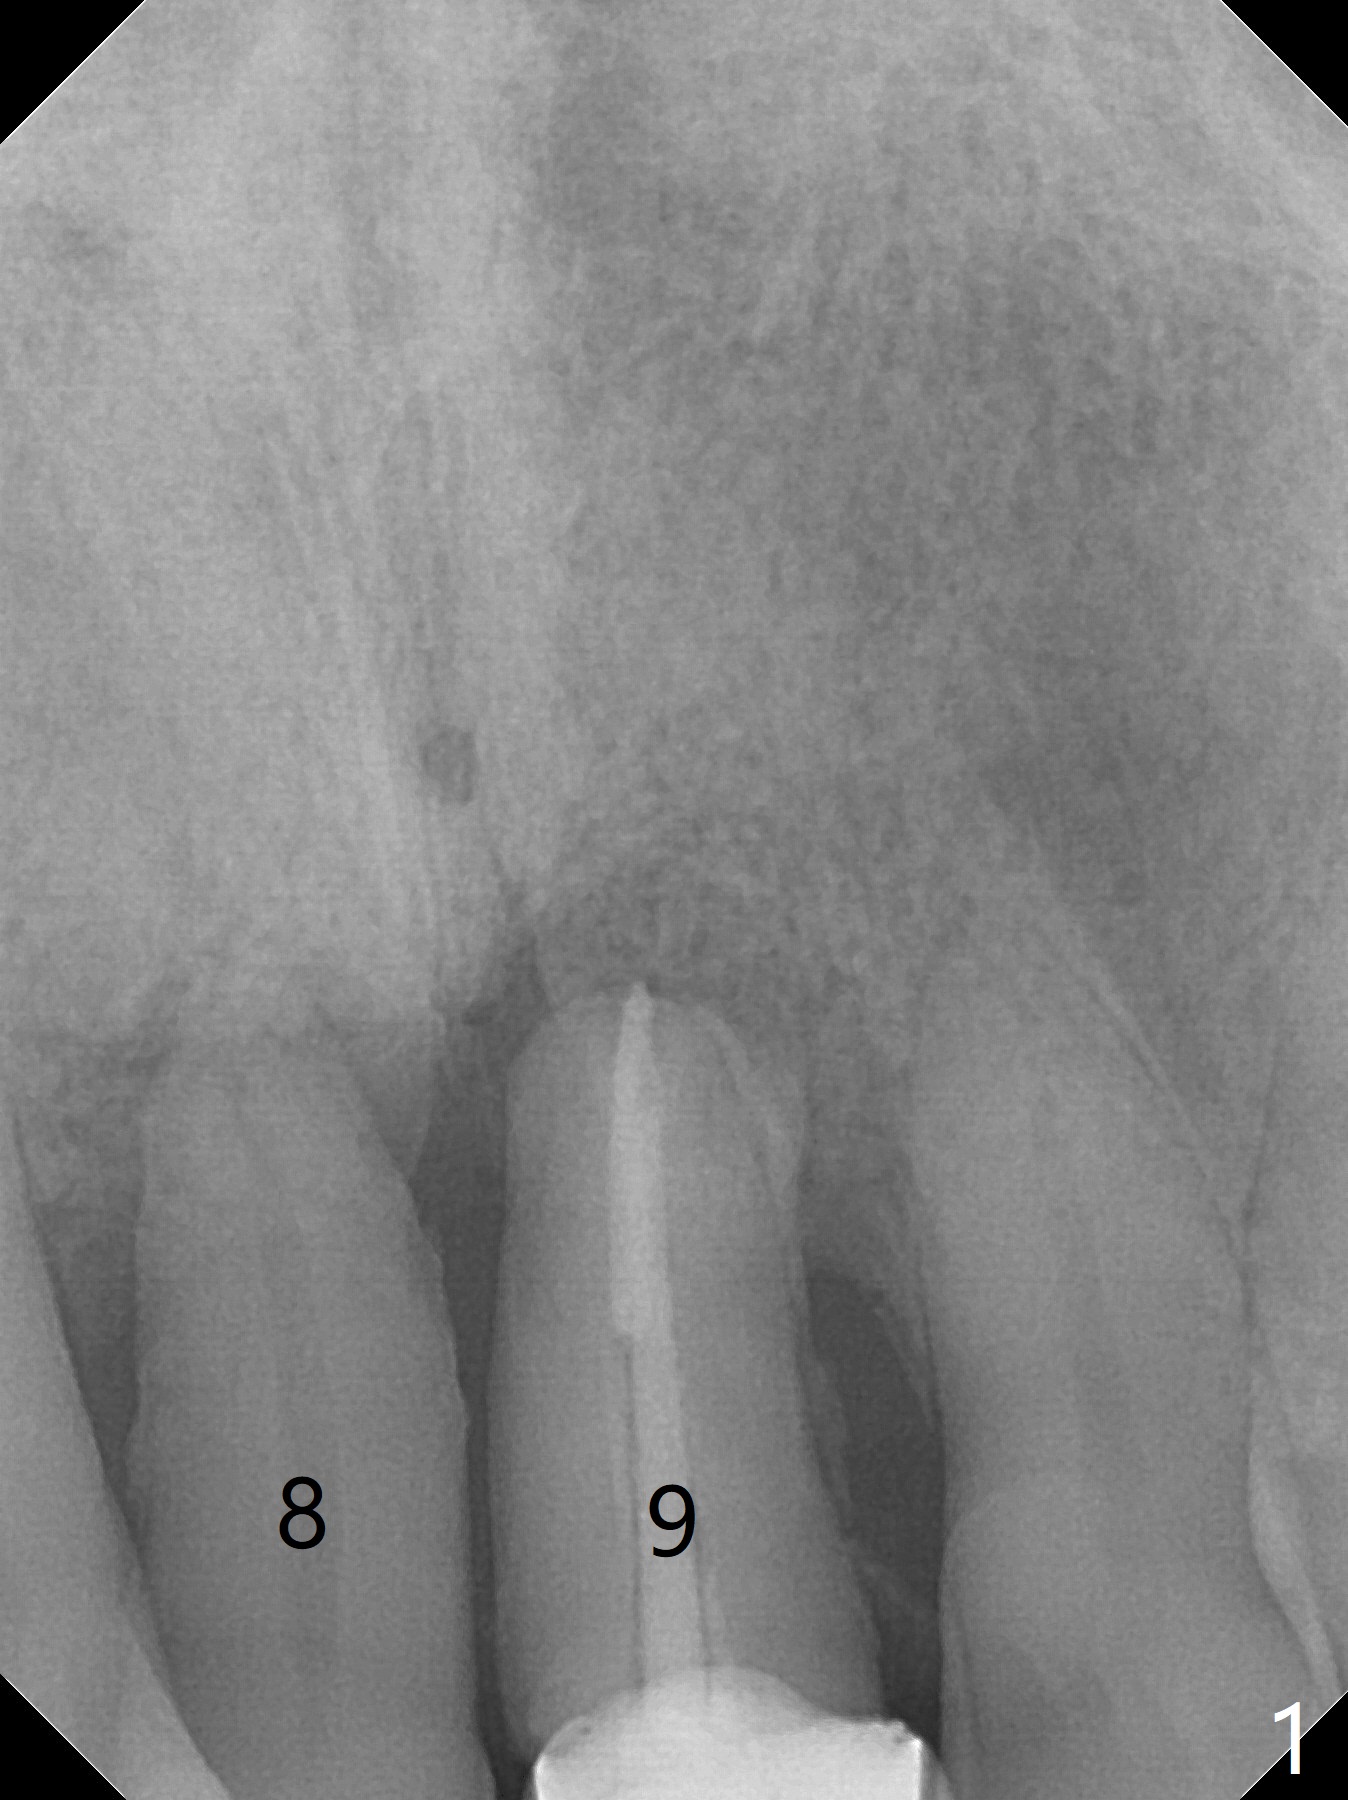

A 59-year-old man requests treatment for buccally displaced upper central incisors (Fig.1,2). It appears that the buccal plate is lost, but the bone height will allow placement of 3.5x13 mm implants with guide (Fig.3). Because of severe infection apical to the tooth #8 (Fig.4,5 *) and truncation of the incisal edges of the upper central incisors during CBCT taking (Fig.6,7 *), guided surgery may not be appropriate. The mesial surfaces of the teeth #7 and 10 and the incisal edges of the lower incisors (*) will be trimmed for immediate provisional. Immediate implants will be placed in the palatal crest of #8 (Fig.6 <) and close to the palatal crest of #9 (Fig.7). Angled abutments are expected (4.5x15 degree, A or B (4 mm cuff). PRF is to be preparedx2 (one for membrane; the other for sticky bone). Take Alginate impression when the patient returns for surgical stent.